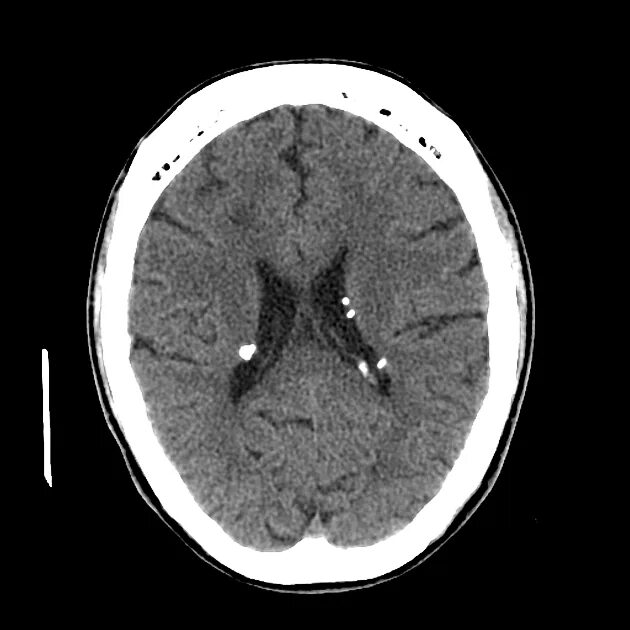

Туберкулезный склероз